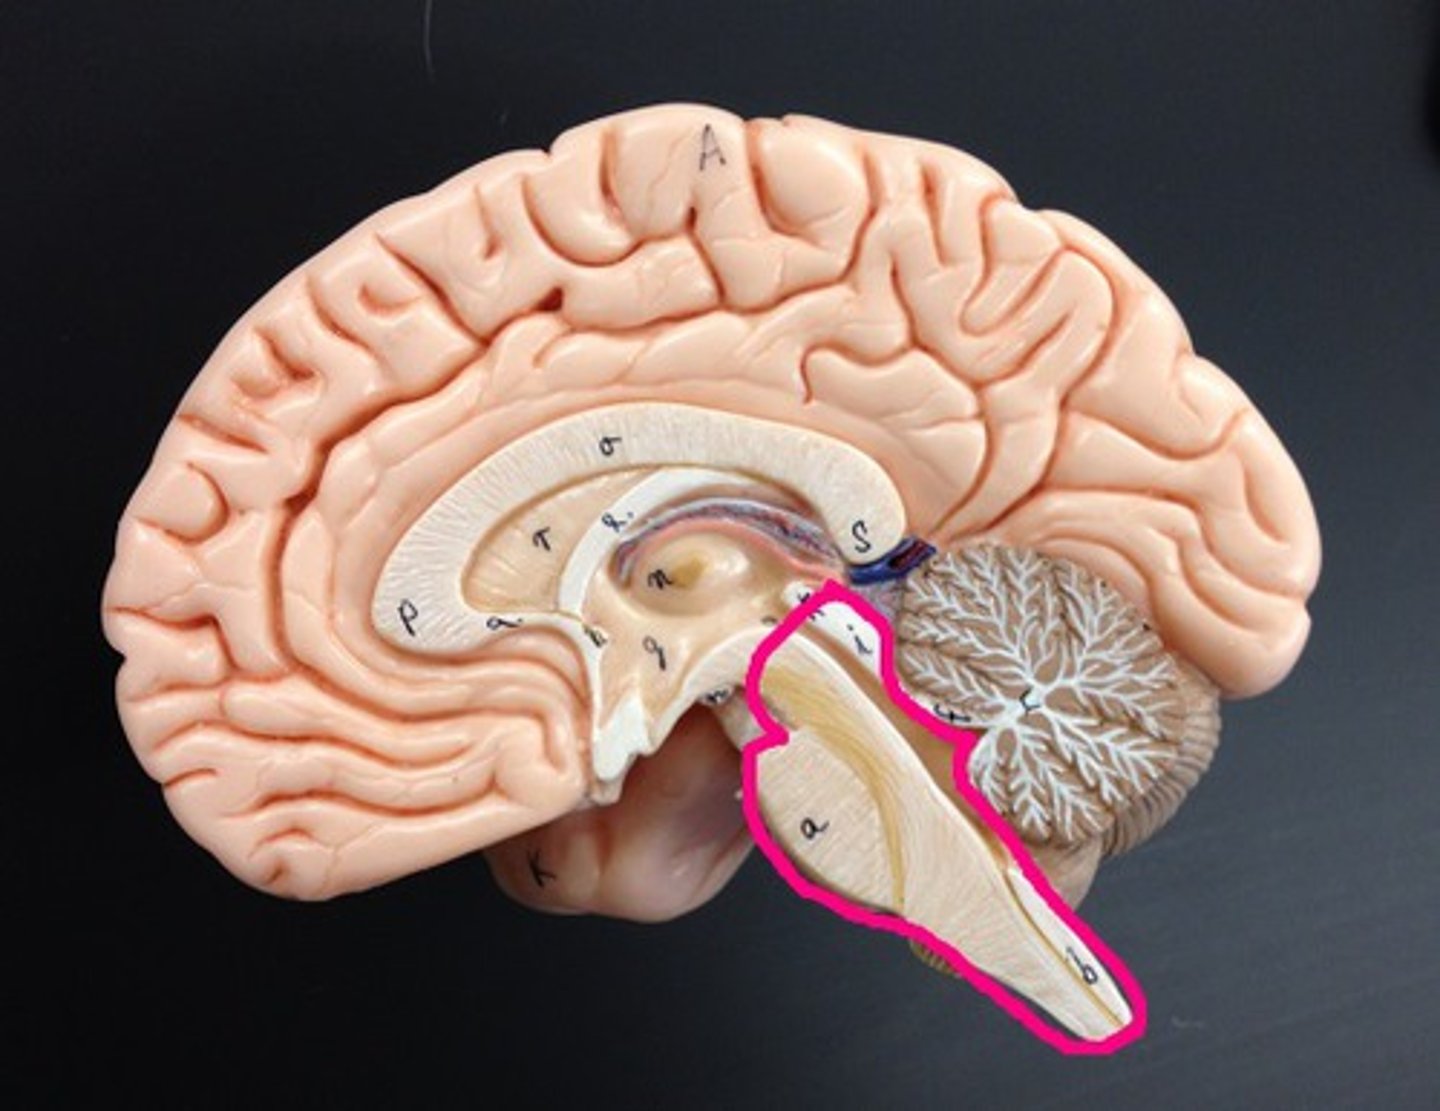

Diencephalon

Sits on top of the brain stem,

Enclosed by the cerebral hemispheres,

Made up of 3 parts: the Thalamus, Hypothalamus, and Epithalamus

Epithalamus

Forms the roof of the 3rd ventricle,

Houses the pineal gland or body (an endocrine gland) (Melatonin production: sleep/wake cycle),

Includes the choroid plexus (forms cerebrospinal fluid- CSF)

Choroid Plexus

Forms Cerebrospinal Fluid

Choroid Plexus

Pineal Gland

Melatonin Production (sleep/wake cycle)

3rd Ventricle

Brain Stem

Cerebellum

Two hemispheres with convoluted surfaces,

Accounts for ~11% of total brain mass,

Provides involuntary coordination of body movements,

Also plays a role in posture and equilibrium

4th Ventricle